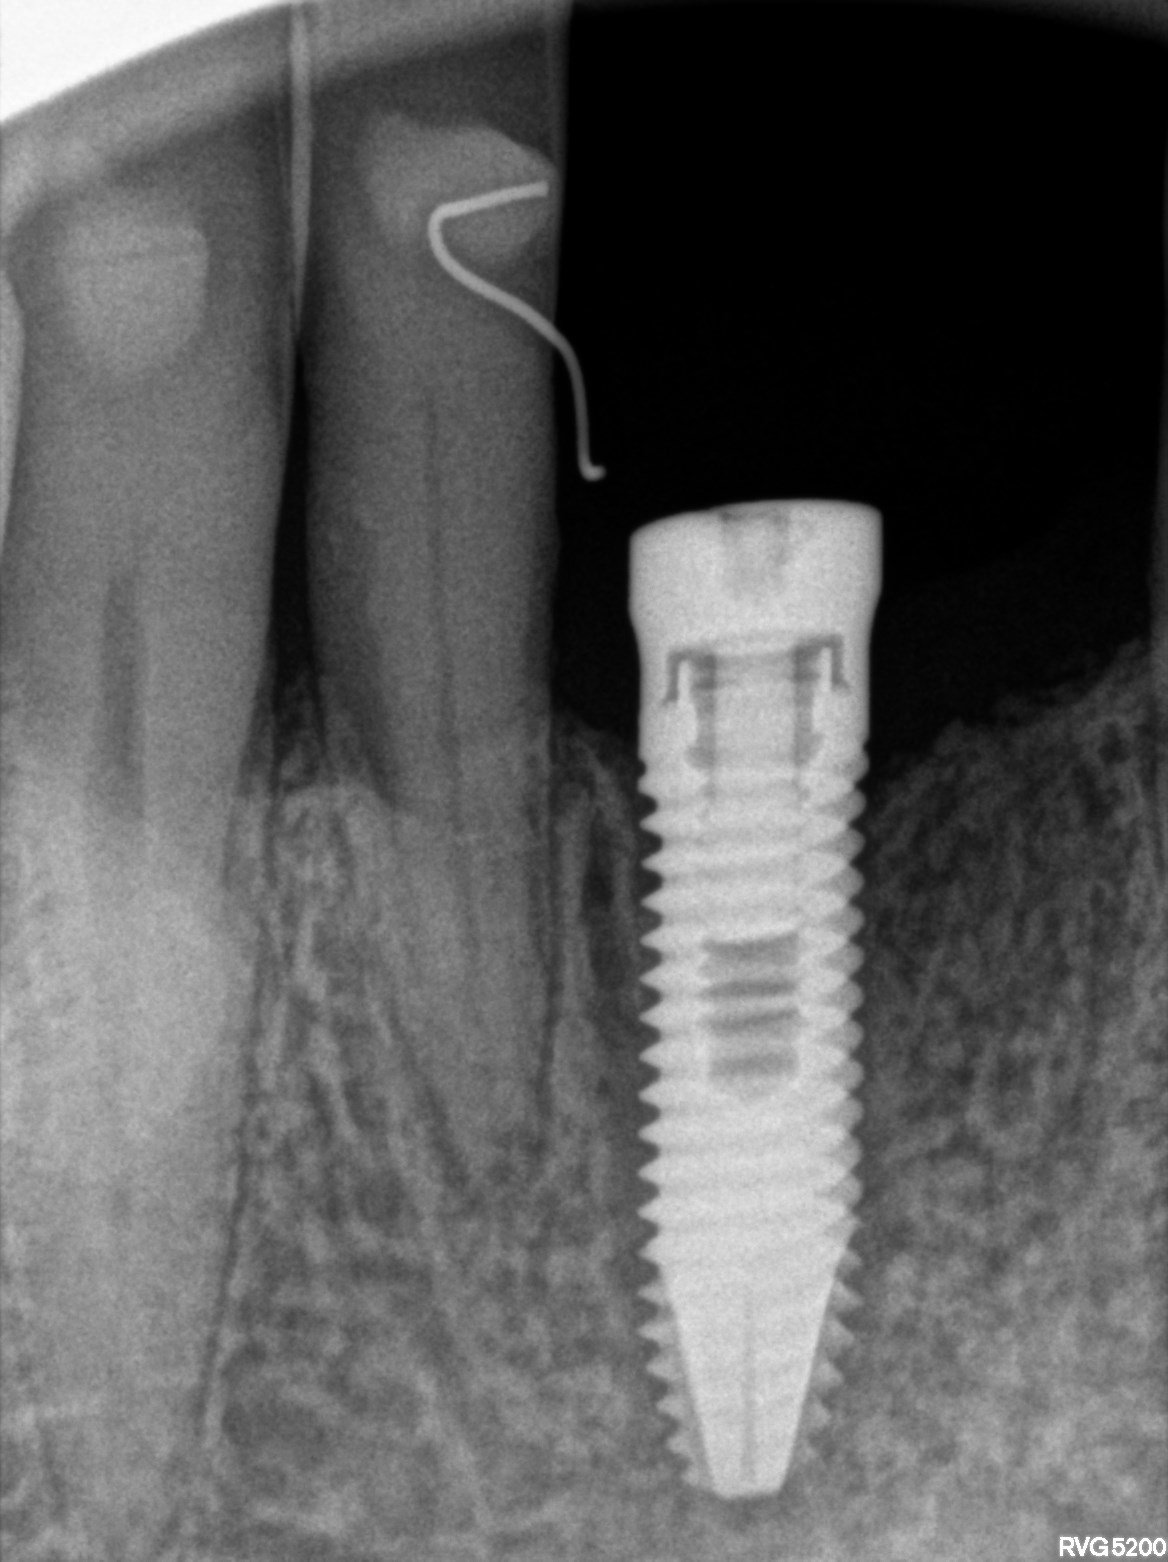

Buenos días, el caso en cuestión es un paciente al que le colocaron un implante en el 4.1 postextracción y lleva más de un año sin realizar la corona. La [...]